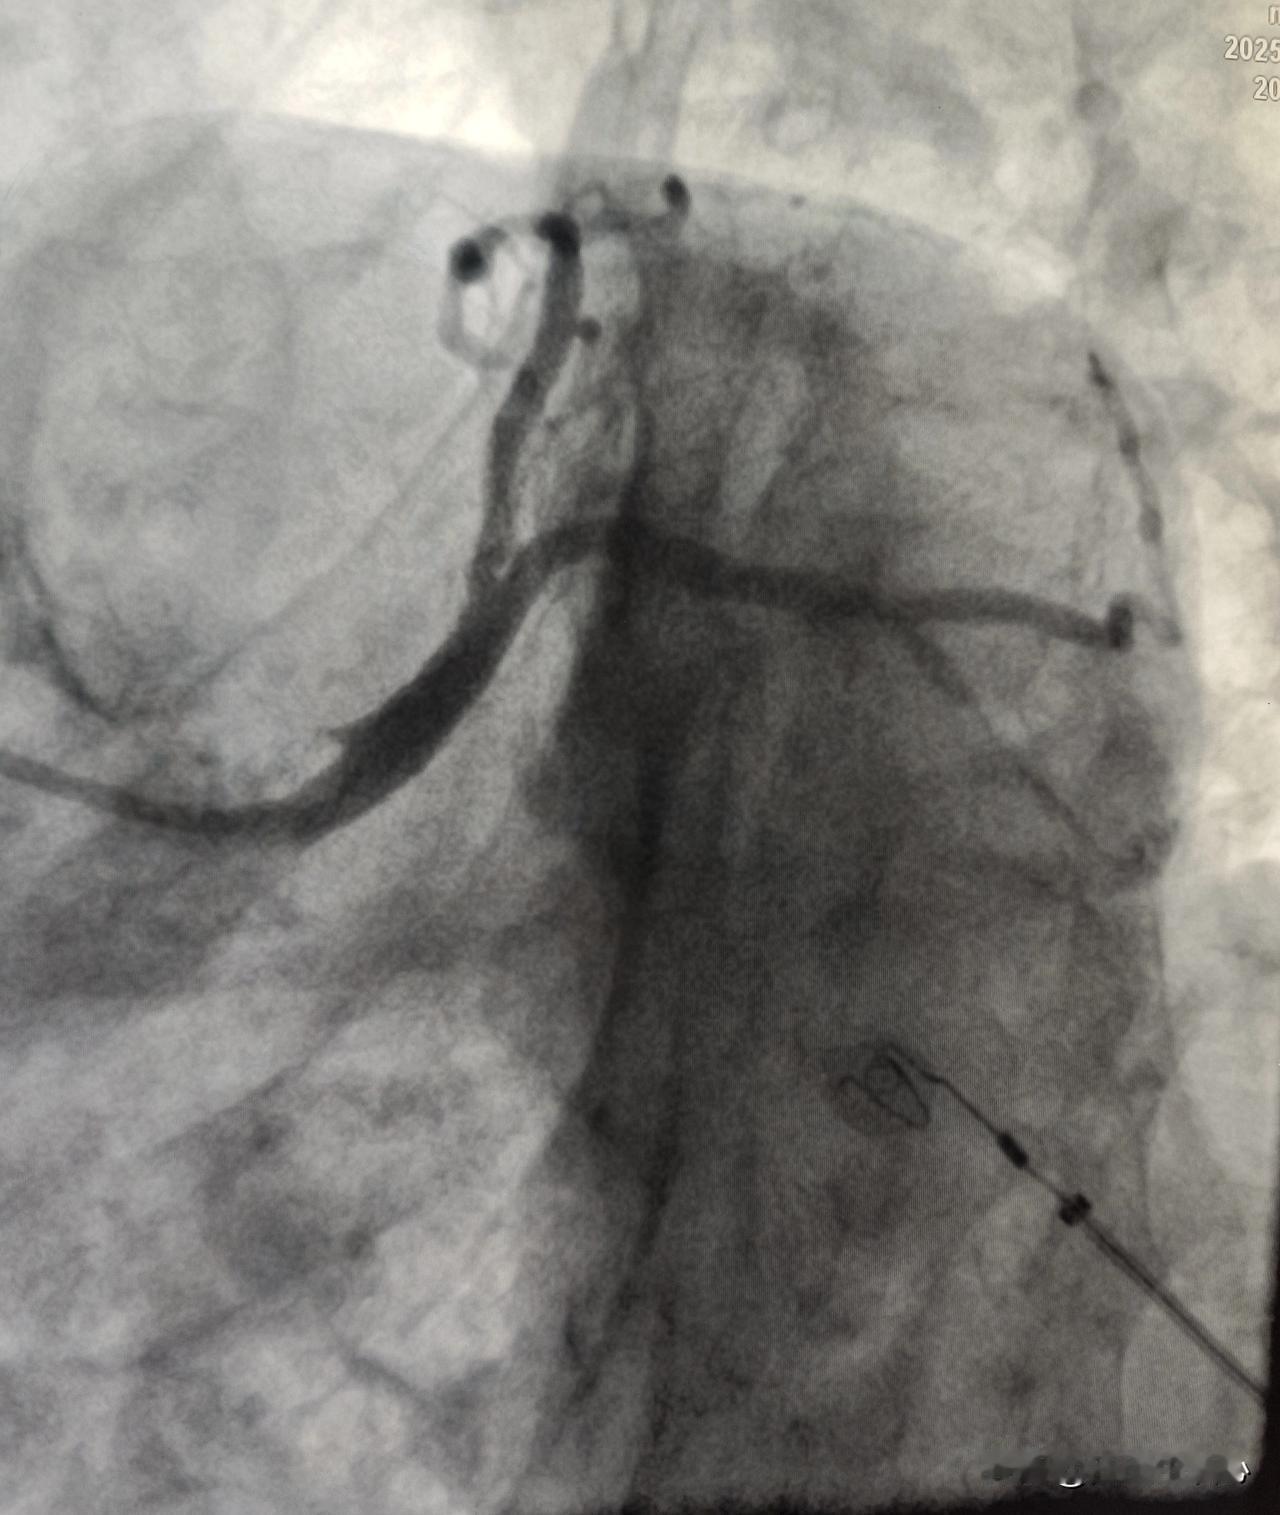

冠状动脉痉挛什么样?快来直观看一下冠状动脉痉挛。

这是一个做冠脉支架的患者,在导